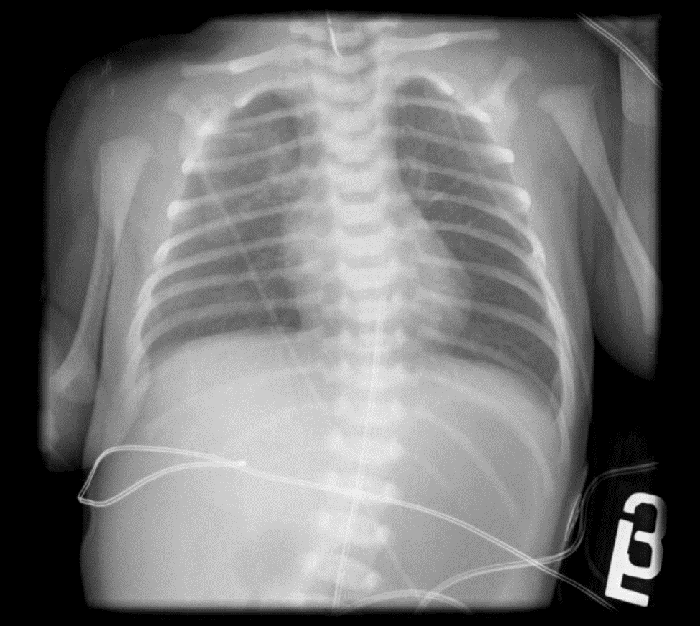

A 2725 g female infant with prenatal history of polyhydramnios was born at 39 weeks by Caesarean section for face presentation. She was placed on continuous positive airway pressure at delivery but quickly weaned to room air without evidence of respiratory distress. Initial x-ray demonstrated a coiled Replogle tube in the upper esophagus, an air-distended stomach, and a paucity of air in the distal gastrointestinal tract concerning for EA/TEF with DA (Figure 1).

Figure 1. Chest radiograph demonstrates a distended gas-filled stomach, and a Replogle tube in the esophagus which met resistance at the proximal esophageal pouch at the level of the clavicle.